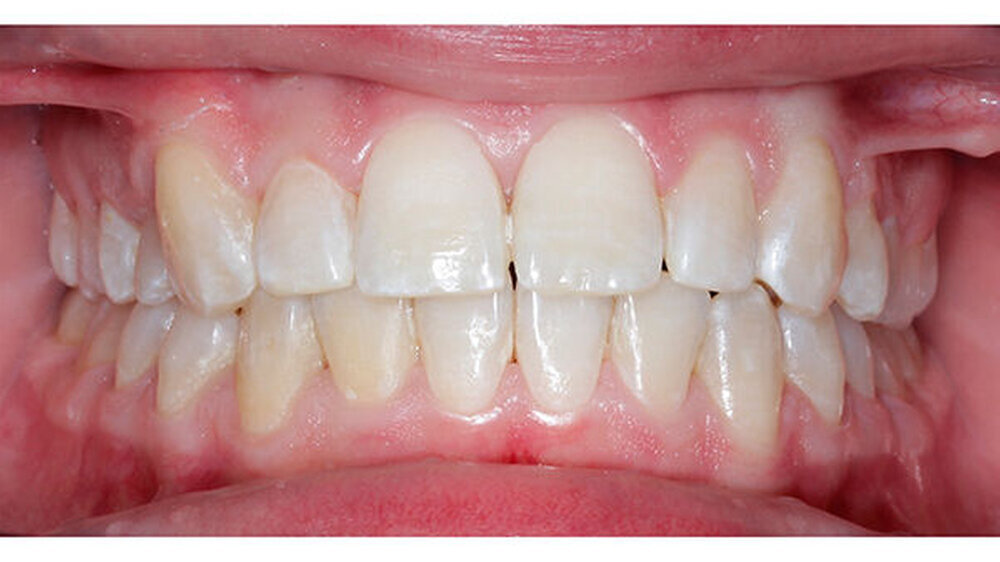

Nach dreijähriger kieferorthopädischer Behandlung konnte die Patientin entbändert werden. Eine Stabilisierungsphase mit herausnehmbaren Essixschienen folgte. Nach Ende der aktiven Behandlungszeit waren die Therapieziele weitgehend erfolgreich umgesetzt worden.

Bei dieser Patientin hätte man die Angulation von Zahn 14 den Torque von Zahn 13 noch etwas besser einstellen können. Die Patientin wünschte sich in der Finishingphase jedoch eine vorzeitige Entbänderung.